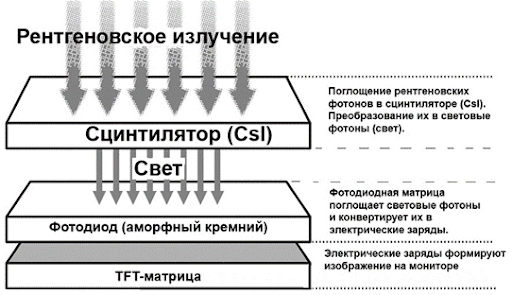

Плоскопанельный матричный детектор представляет собой электронное устройство прямоугольной формы, размещенное в металлическом или пластиковом корпусе, который защищен карбоновым экраном. Карбон пропускает рентгеновское излучение, не оказывая влияния на качество изображения. Внутри корпуса находится светочувствительная матрица, которая может быть покрыта слоем сцинтиллятора, материал которого преобразует рентгеновское излучение в видимый свет. Сцинтилля́торы — это вещества, излучающие свет при поглощении ионизирующего излучения (гамма-квантов, электронов, альфа-частиц, электромагнитных волн рентгеновского излучения).

Существует два вида преобразования рентгеновского излучения в электрический сигнал:

1. Непрямое – рентгеновское излучение сначала преобразуется в свет при помощи сцинтиллятора, а затем в электрический сигнал при помощи светочувствительной матрицы из аморфного кремния (a-Si).